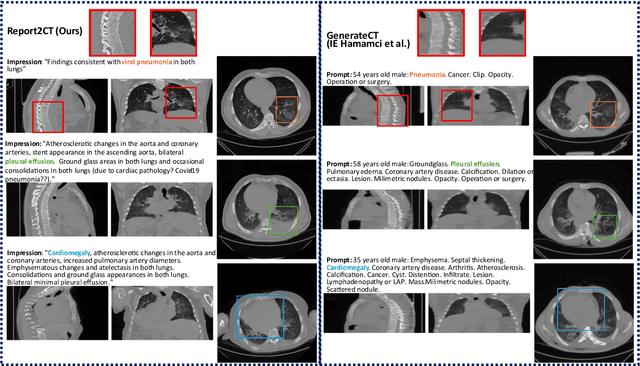

Abstract:Text to image latent diffusion models have recently advanced medical image synthesis, but applications to 3D CT generation remain limited. Existing approaches rely on simplified prompts, neglecting the rich semantic detail in full radiology reports, which reduces text image alignment and clinical fidelity. We propose Report2CT, a radiology report conditional latent diffusion framework for synthesizing 3D chest CT volumes directly from free text radiology reports, incorporating both findings and impression sections using multiple text encoder. Report2CT integrates three pretrained medical text encoders (BiomedVLP CXR BERT, MedEmbed, and ClinicalBERT) to capture nuanced clinical context. Radiology reports and voxel spacing information condition a 3D latent diffusion model trained on 20000 CT volumes from the CT RATE dataset. Model performance was evaluated using Frechet Inception Distance (FID) for real synthetic distributional similarity and CLIP based metrics for semantic alignment, with additional qualitative and quantitative comparisons against GenerateCT model. Report2CT generated anatomically consistent CT volumes with excellent visual quality and text image alignment. Multi encoder conditioning improved CLIP scores, indicating stronger preservation of fine grained clinical details in the free text radiology reports. Classifier free guidance further enhanced alignment with only a minor trade off in FID. We ranked first in the VLM3D Challenge at MICCAI 2025 on Text Conditional CT Generation and achieved state of the art performance across all evaluation metrics. By leveraging complete radiology reports and multi encoder text conditioning, Report2CT advances 3D CT synthesis, producing clinically faithful and high quality synthetic data.